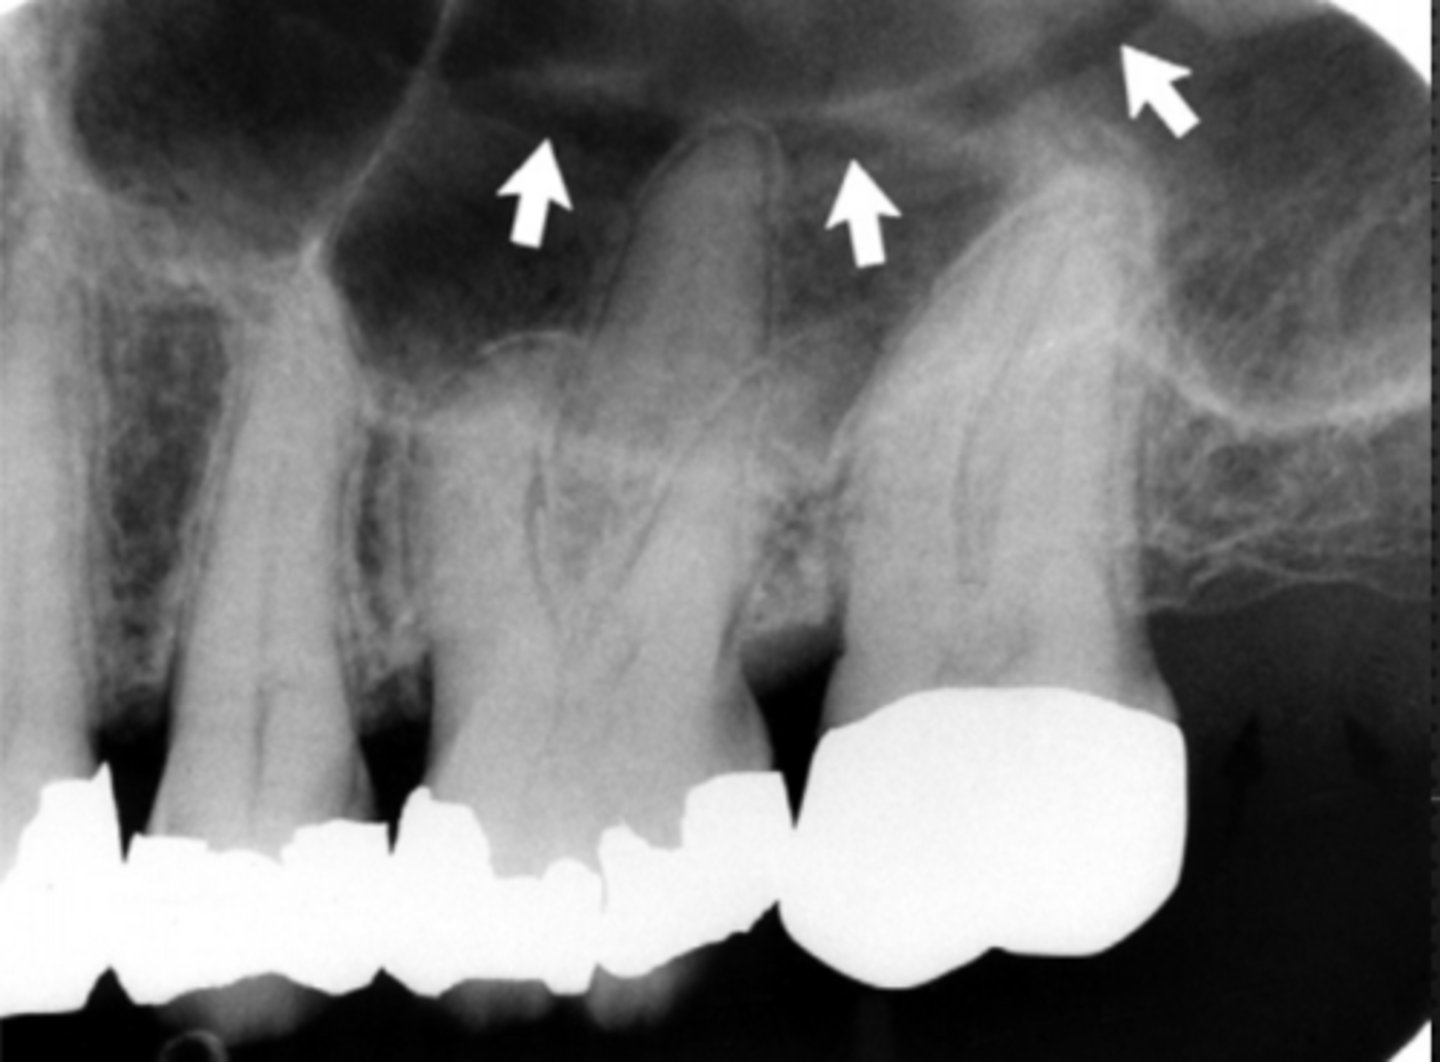

54

New cards

Submandibular fossa

Name the radiolucent area indicated by the arrows

<p>Name the radiolucent area indicated by the arrows</p>